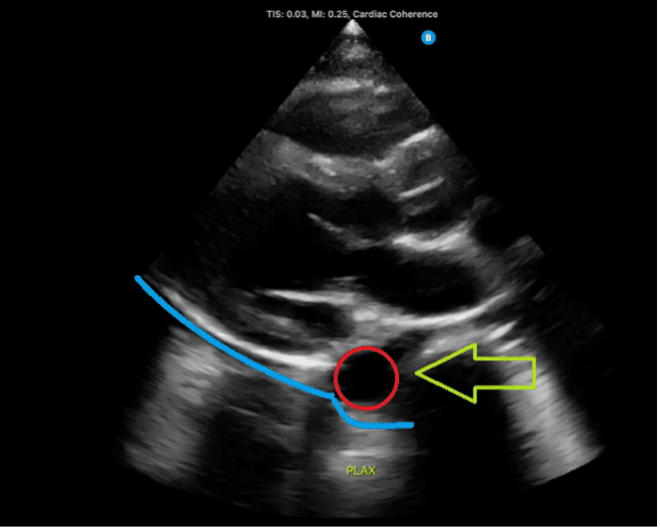

Figure 3: Normal parasternal long-axis view demonstrating the descending aorta, indicated by the red circle and green arrow. A fluid collection located below the descending aorta, denoted by the blue line, would suggest a pleural effusion.